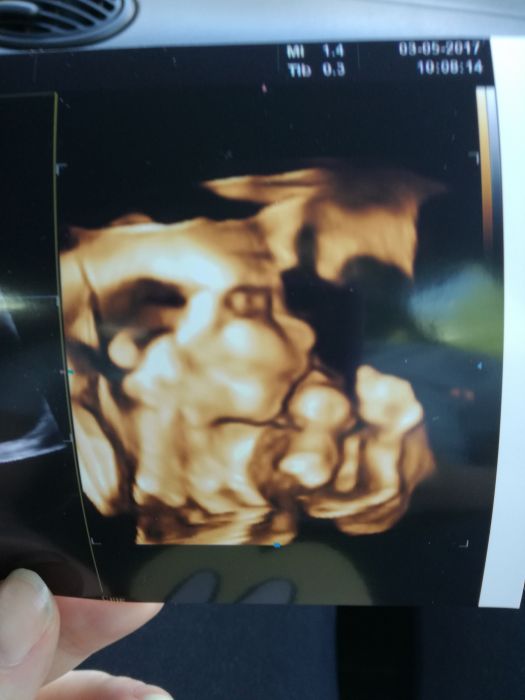

Tak dnesni velky utz taky za nami,vse je jak.ma byt :) pindik nam neupadl,takze Adamek 325g,TP 20.9. ?